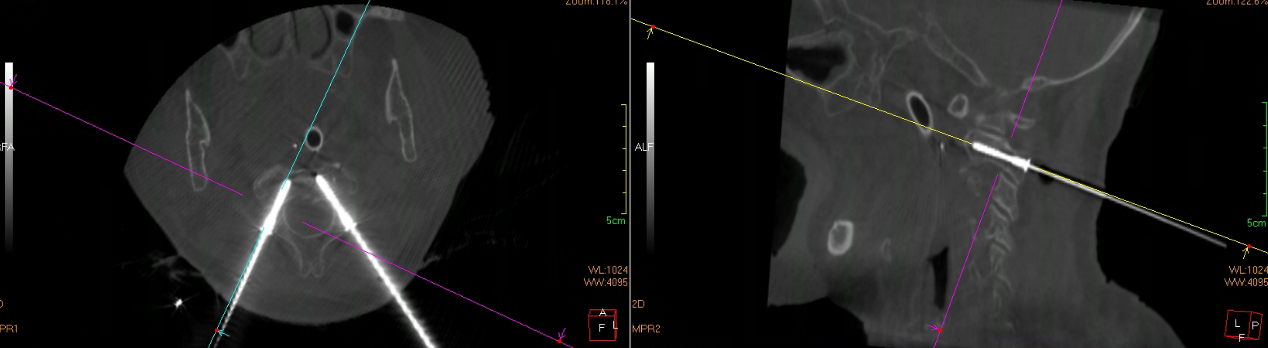

骨科手术机器人术中精准规划置钉